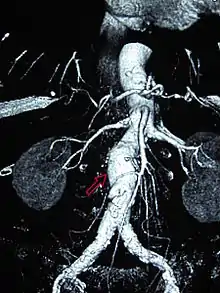

Einstein's aneurysm repair

In December 1948, Nissen admitted Albert Einstein to Jewish Hospital for removal of intestinal cysts. However, the scientist was also suffering from an abdominal aortic aneurysm (AAA).[6] An aneurysm is a dilatation that occurs in a blood vessel. In the portion of the aorta that runs through the abdomen, aneurysms are typically asymptomatic until rupture is imminent.[7] AAA rupture can cause immediate death from exsanguination.[8] Definitive surgical treatment for AAA had not been devised in the 1940s. Beginning in 1943, reinforcement with cellophane had been used to induce fibrosis in the vessel, decreasing the risk of rupture. Nissen wrapped the aneurysm with cellophane and Einstein recovered from the surgery.[6]

Upon his hospital discharge, Einstein was surrounded by photographers and he was photographed with his tongue sticking out at them. He sent an autographed newspaper clipping of the photo to Nissen with the inscription "To Nissen my tummy / The world my tongue."[9] Einstein lived for several years after Nissen wrapped his AAA in cellophane.[6] Einstein died in a Princeton, New Jersey hospital in 1955. Initial news reports listed gallbladder inflammation as the cause of death.[10] However, his medical team had suspected gallbladder irritation resulting from a leaking AAA.[11] An autopsy conducted by pathologist Thomas Harvey showed that he died of a leaking AAA.[12]